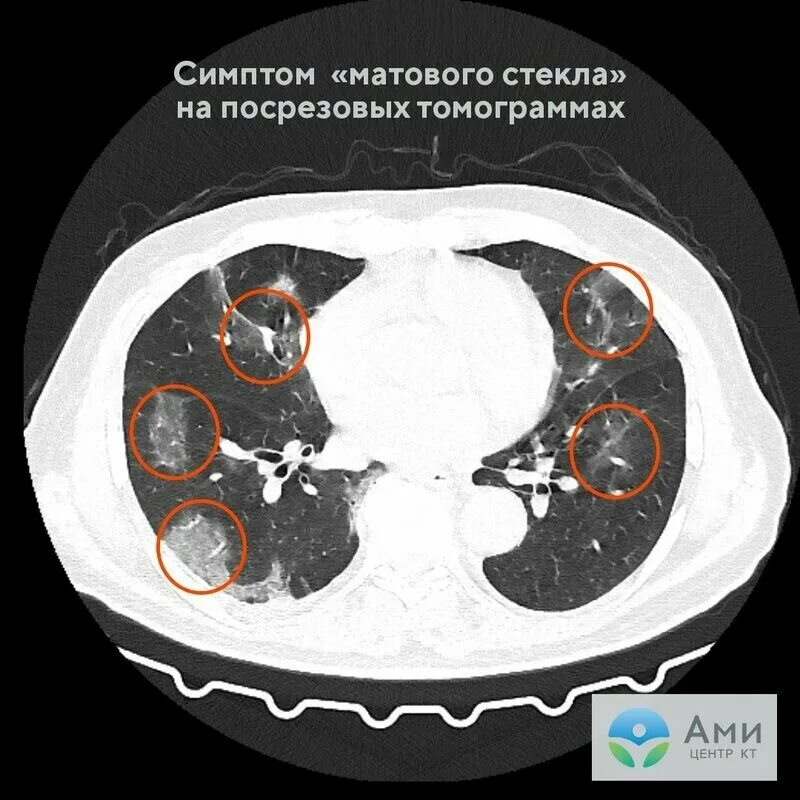

Кт после ковид